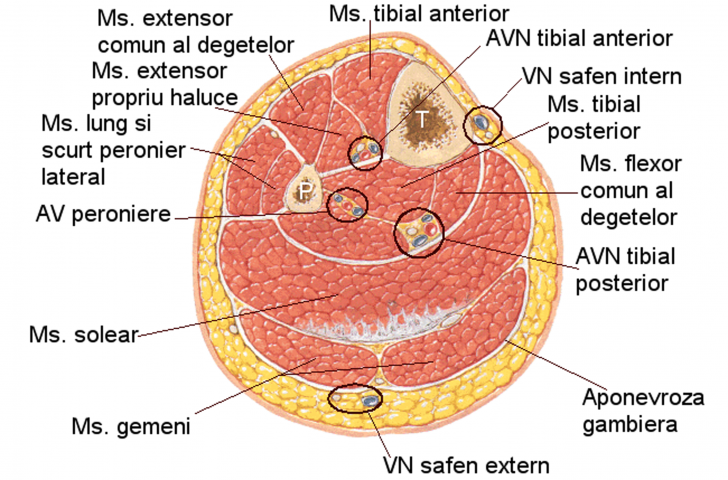

AMPUTATIA DE GAMBA

AMPUTATIA DE GAMBA I. DEFINITIE Amputatia de gamba este interventia chirurgicala prin care se realizeaza indepartarea membrului inferior de la nivelul gambei. II. ISTORIC Chirurgia de amputatie este una din celeCiteste tot ... 4314 cuvinte